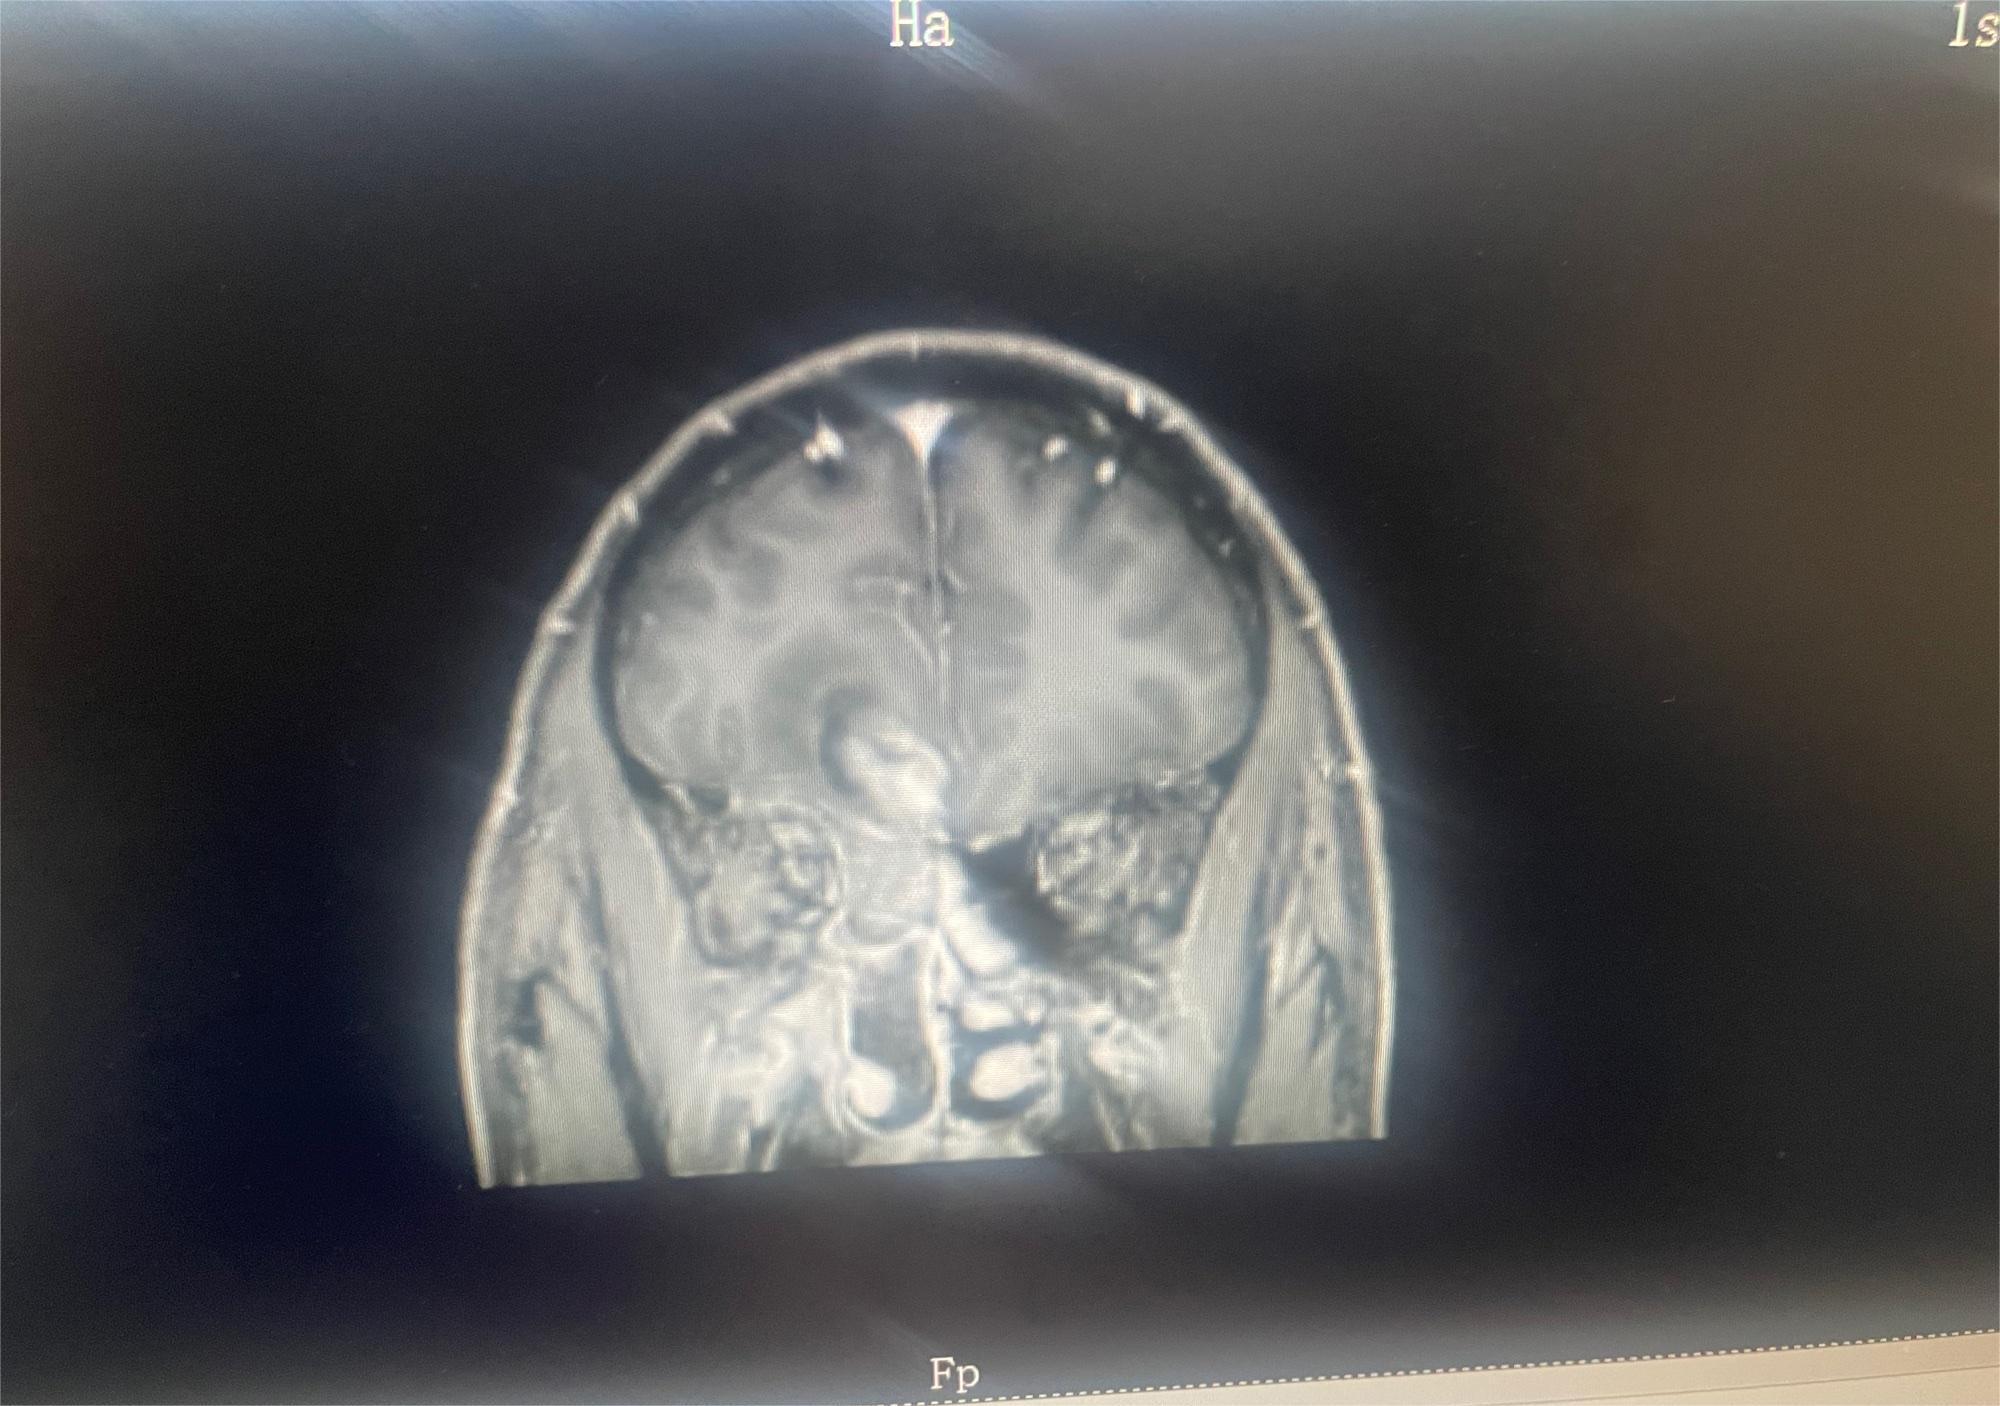

Kawahi 001月07日 09:33 患者家属肿瘤主要位于脑干,医生都说做不了切除手术,现在做了活检,准备去做放疗,但也几乎无济于事,不知道还会不会有可能有其他治疗方...

幻灭人海 02024-11-19 患者家属我妈妈确诊脑胶质瘤,现在在沧州中心医院脑科,医生说恶性程度很高,手术肯定瘫痪,建议保守治疗,我弟去了天津肿瘤医院,让做M...